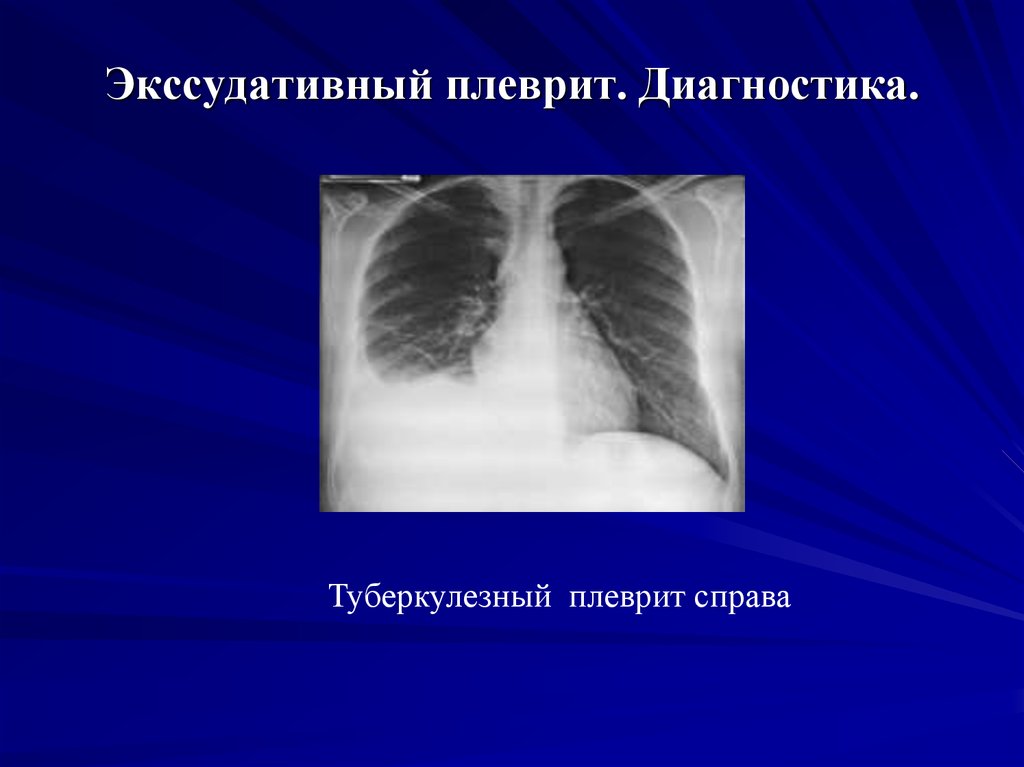

Диагностика плеврального выпота: что нужно знать